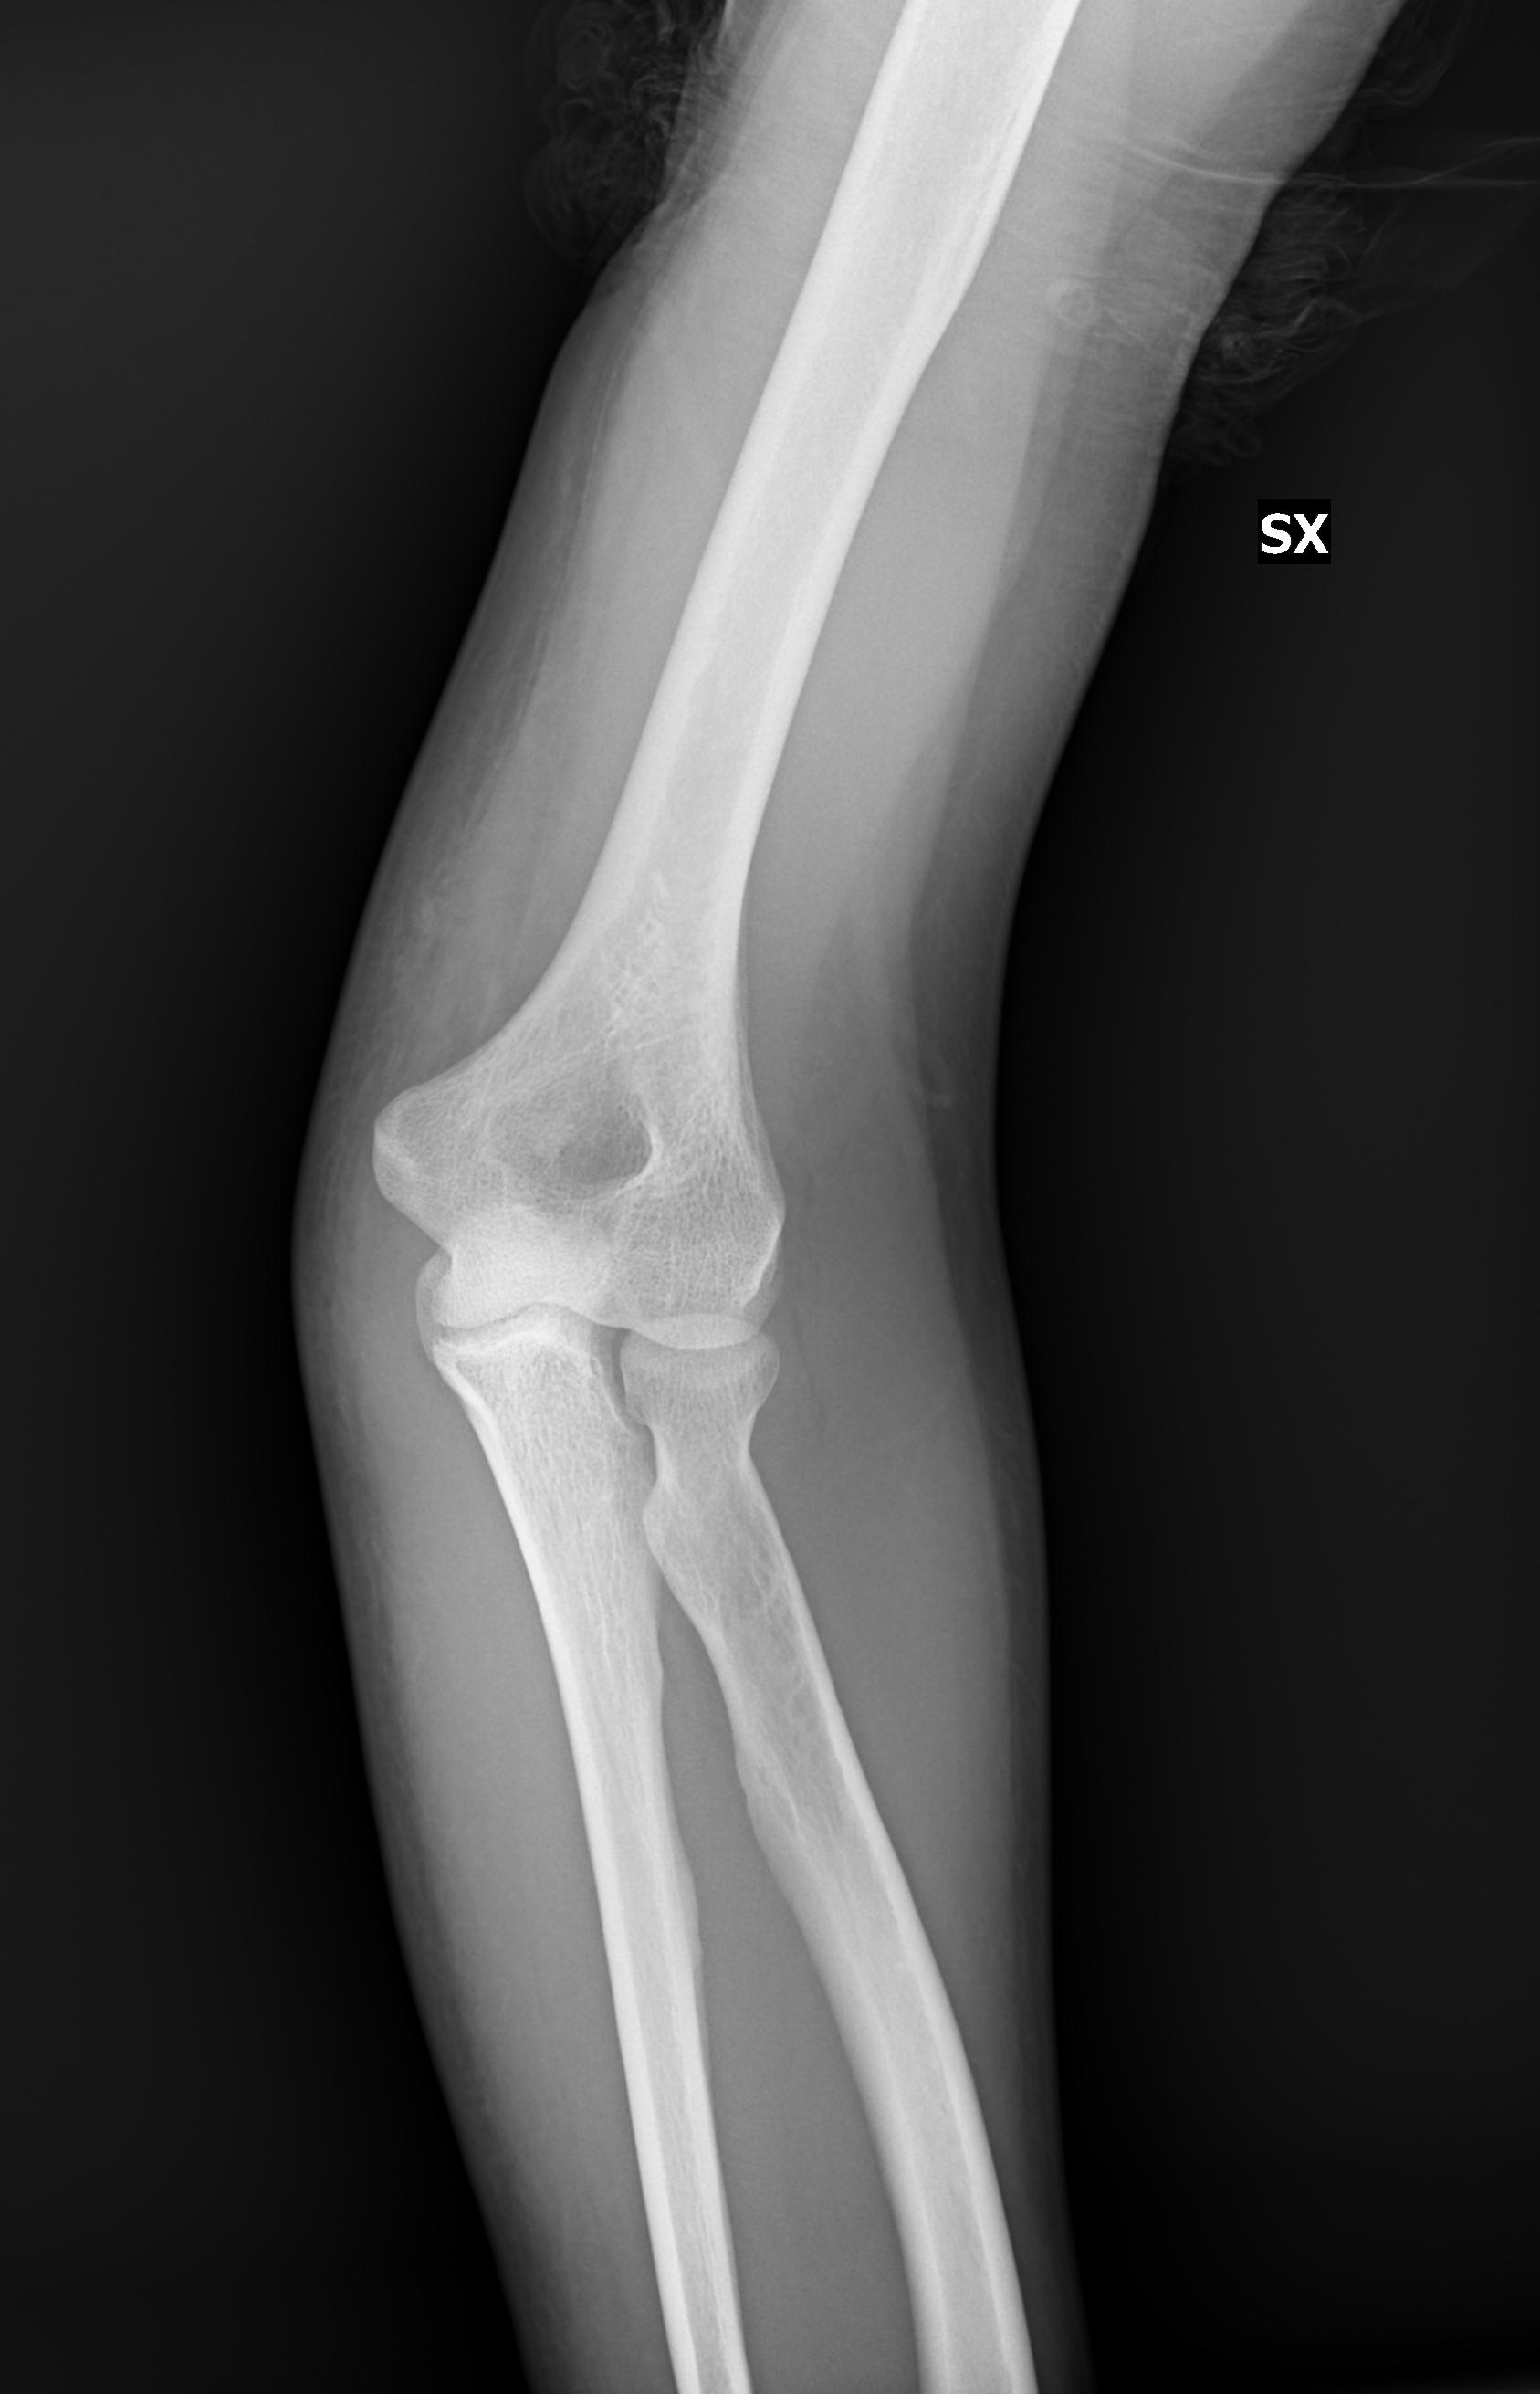

Giorno 16 Gen camminando cado inciampando in un dislivello. Al pronto soccorso fanno Rx al Gomito (due proiezioni), polso e mano Sx . Dopo visita ortopedica la diagnosi risulta: TRAUMA CONTUSIVO ARTO SUP SX.

Giorno 21 rifaccio i Rx altrove e mi risulta invece: DISTACCO LAMELLARE DEL CAPITELLO RADIALE.

1) E’ possibili capire di che entità è la lesione? Mi potrebbero bastare i 17/18 gg di reggibraccio? (invio in jpg i raggi fatti successivamente).

invio in allegato i raggi effettuati

IMG00002.jpg

[ 101.89 KiB | Osservato 976 volte ]

IMG00001.jpg

[ 147.99 KiB | Osservato 976 volte ]